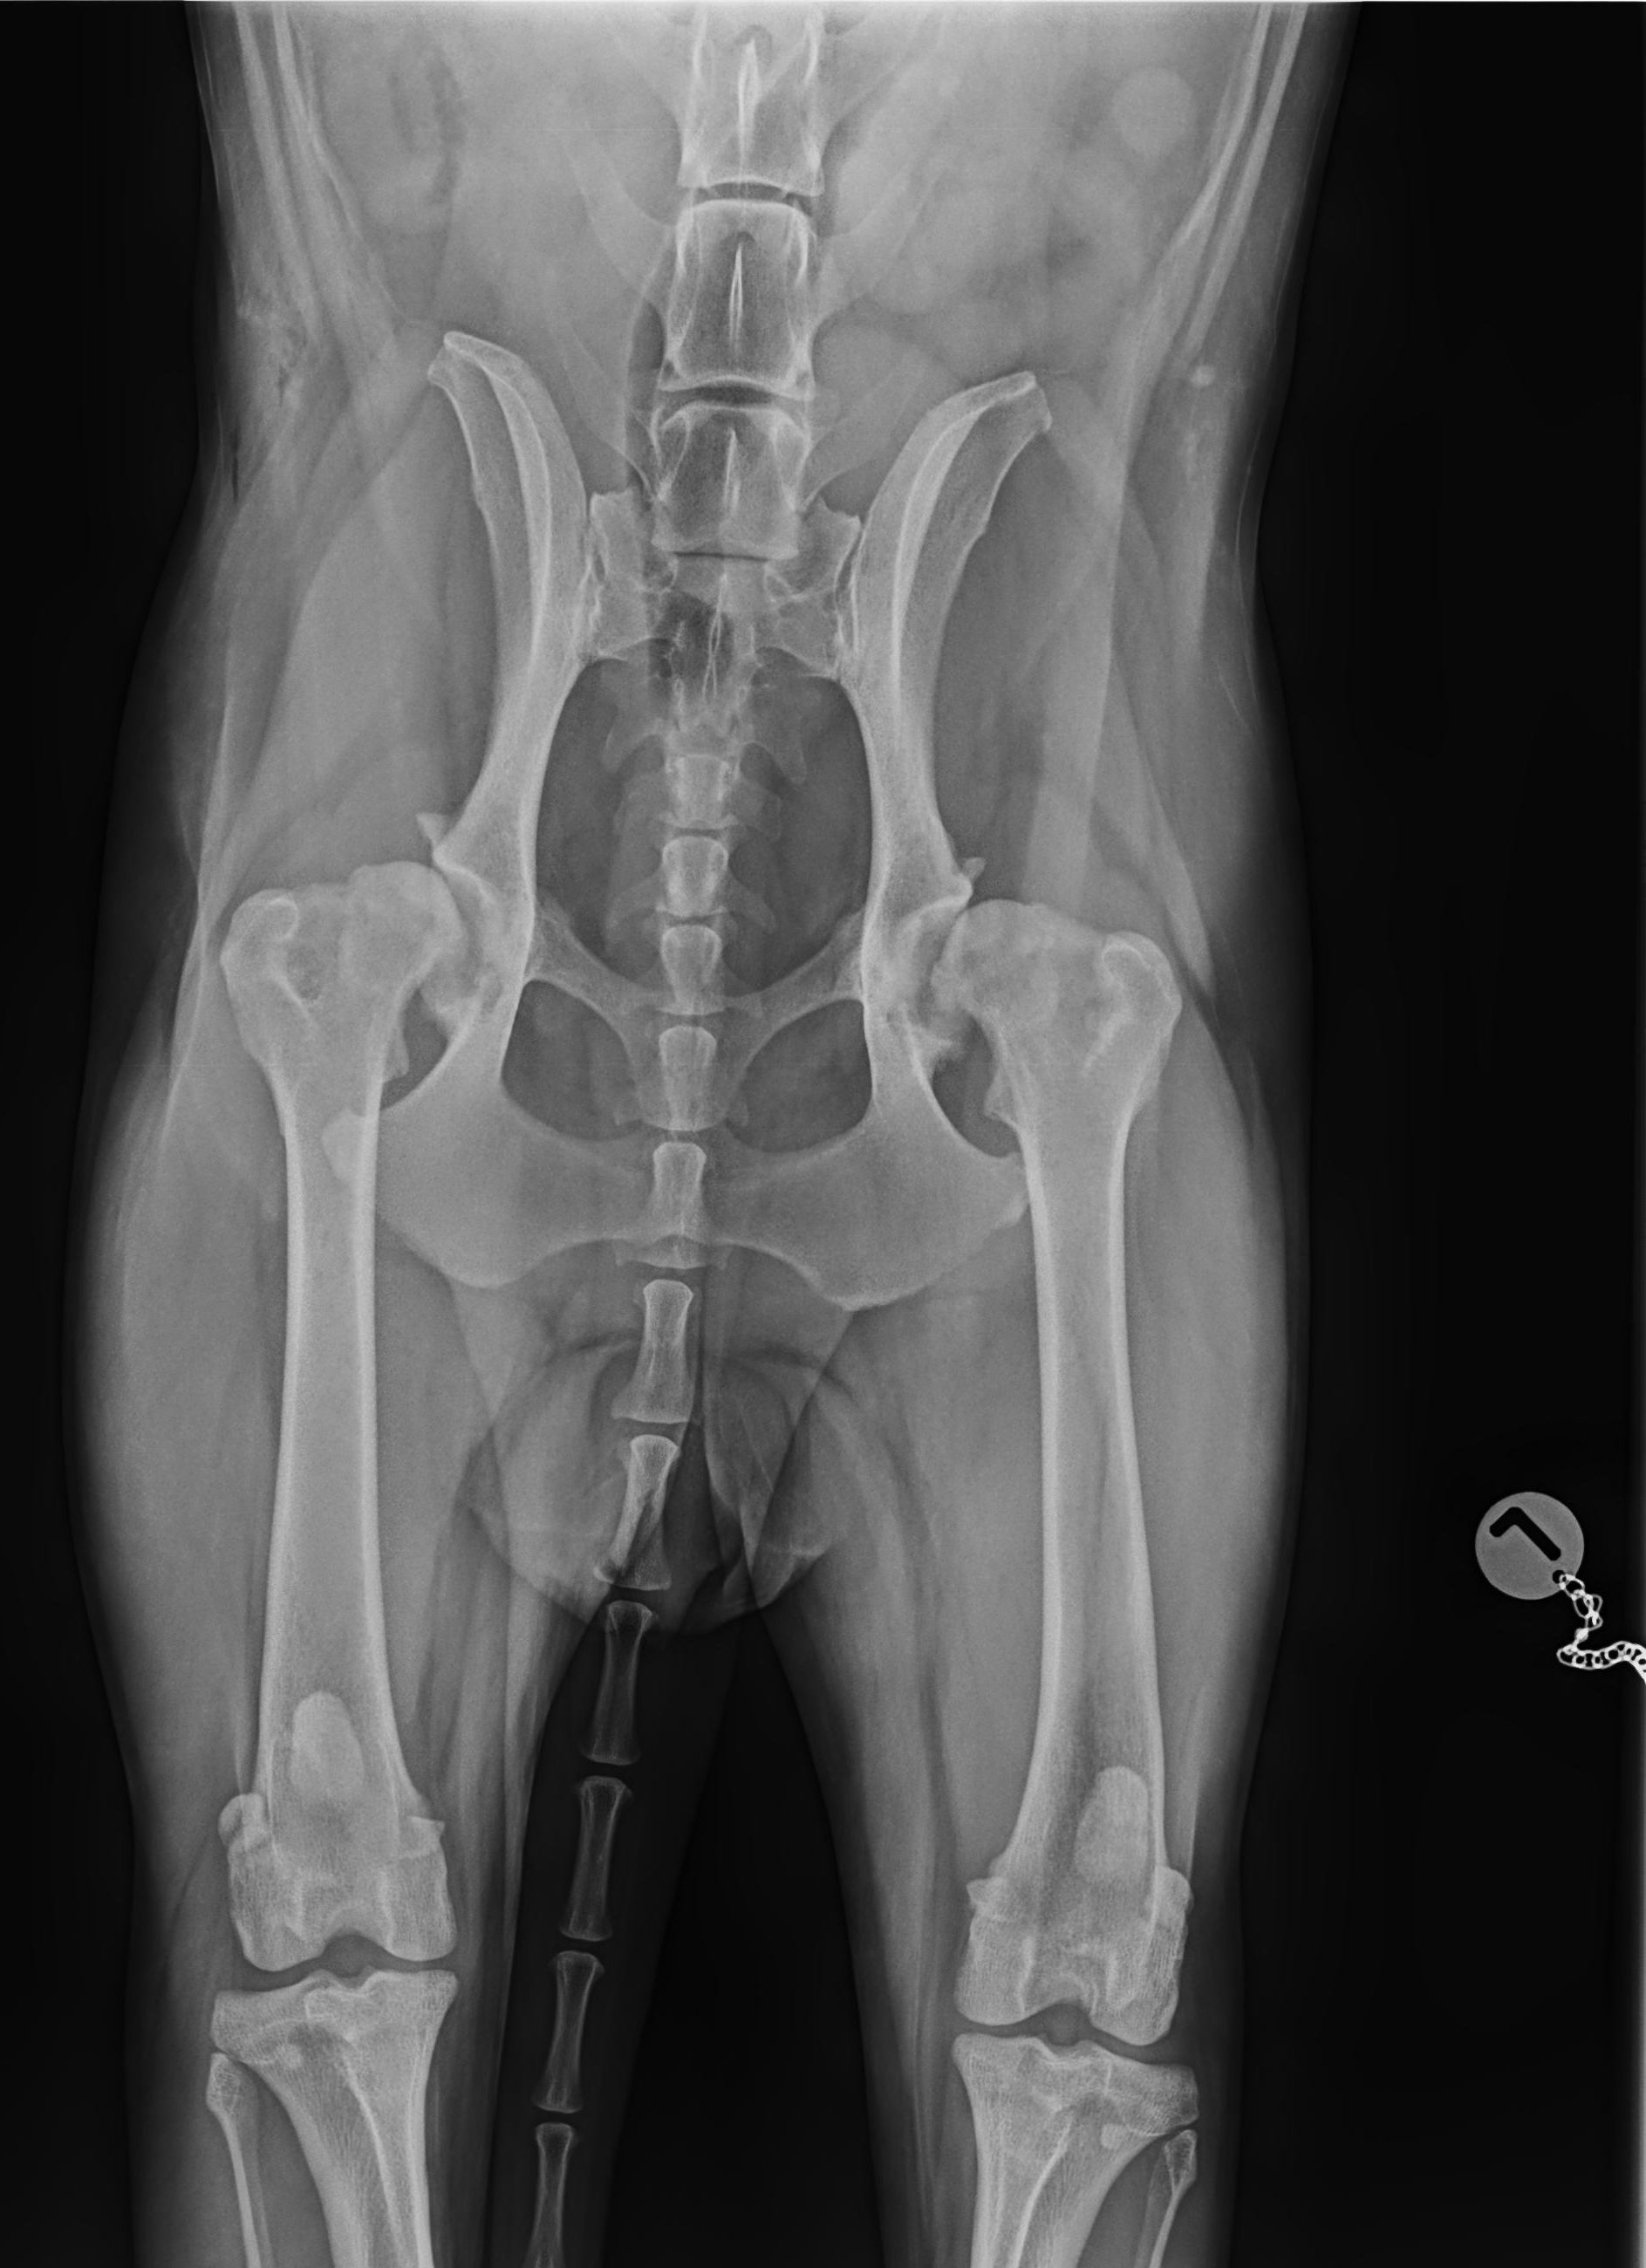

HD – Röntgenuntersuchung der Hüfte

HD steht für Hüftgelenksdysplasie und bedeutet eine Fehlentwicklung des Hüftgelenks. Betroffen sind davon vor allem Hunde großer Rassen. Die Erkrankung hat genetische (angeborene) Ursachen, aber auch Fehlfütterung oder eine Fehlbelastung können eine Rolle spielen. Eine frühzeitige Diagnose ist daher wichtig, da bis zum 10. Lebensmonat operative Korrekturen durchgeführt werden können. Werden diese bei einer HD Erkrankung nicht durchgeführt, kommt es unausweichlich zu einer Arthrose des betroffenen Gelenks. Als therapeutische Maßnahme ist dann die Implantation eines künstlichen Hüftgelenks möglich.

Daher empfehlen wir ein „Vorröntgen“ mit 6 Monaten, welches bereits sehr aussagekräftig ist. Ab dem 12. Lebensmonat kann dann ein offizielles Röntgenbild gemacht werden (zur Zuchtzulassung bzw. zur Zulassung zur Ausbildung zum Assistenzhund).

HD Grad A

HD Grad E